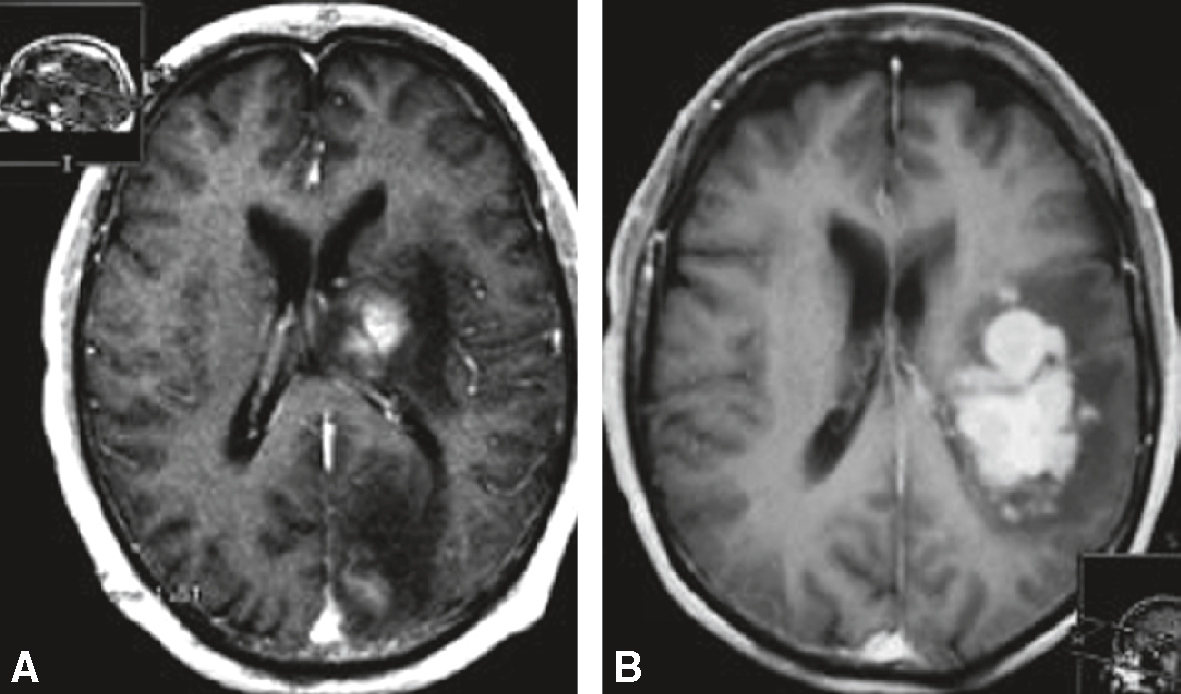

IRM cérébrale réalisée chez un patient de 67 ans traité pour un adénocarcinome bronchique avec une hémiparésie gauche récente. Présence de deux lésions intracérébrales hémisphériques droites, bien limitées et arrondies, développées respectivement dans la région frontale antérieure et au niveau du lobule paracentral (région centrale interne), en hyposignal T1 et en hypersignal T2, entourées d’un œdème important. Effet de masse sur le ventricule latéral droit avec effacement partiel des cornes frontale et occipitale. Après injection, important rehaussement des deux lésions permettant de les distinguer de l’œdème. A. T1 sagittal. B. T1 axial. C. T1 axial après injection. D. T1 axial après injection. E. T1 sagittal après injection.

Série d’IRM cérébrales réalisées chez un patient de 67 ans atteint d’un adénocarcinome bronchique, présentant une hémiparésie gauche récente. L’image A en coupe sagittale montre une masse ronde bien délimitée en région frontale droite avec œdème périlésionnel, associée à une discrète prise de contraste. Les coupes axiales B et C révèlent plusieurs métastases, identifiables par leur hypersignal en T2 avec effet de masse et déplacement des structures médianes. La présence d’un important œdème vasogénique autour des lésions est visible, contribuant à la symptomatologie. Les images D et E confirment l’aspect nodulaire des métastases avec rehaussement périphérique après injection de gadolinium, suggérant une atteinte secondaire du parenchyme cérébral d’origine néoplasique.

Lésions intracérébrales généralement paraventriculaires ou près des espaces sous-arachnoïdiens, prenant fortement le contraste de manière homogène. Les lymphomes sont très sensibles à la corticothérapie et les images peuvent « disparaître » en délai bref (1 ou 2 semaines), rendant difficile le repérage stéréotaxique, mais aussi l’interprétation anatomopatholo-gique. A. Exemple 1. IRM cérébrale chez une patiente de 71 ans avec ralentissement idéomoteur depuis quelques mois; séquence axiale T1 après injection. B. Exemple 2. IRM cérébrale chez un patient présentant une confusion récente; séquence axiale T1 après injection.

Les deux coupes axiales T1 injectées (A et B) montrent des lésions nodulaires intracérébrales, situées de manière prédominante dans la région paraventriculaire droite, en contact avec le corps calleux et les structures périventriculaires. Sur l’image A, la lésion apparaît en iso- à léger hypersignal avec un effet de masse modéré. Sur l’image B, après injection de gadolinium, on observe une prise de contraste intense, homogène et bien délimitée. Ce type d’aspect est évocateur de lésions d’origine infectieuse ou tumorale, souvent observées dans des contextes d’immunodépression, comme les lymphomes cérébraux primitifs ou les toxoplasmoses cérébrales.